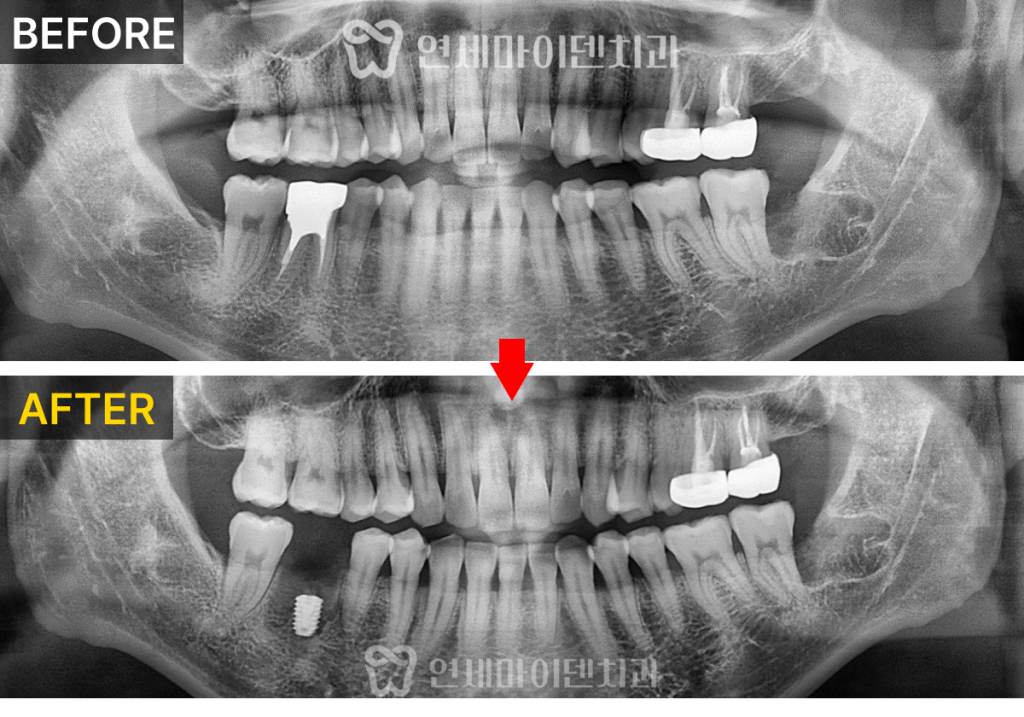

발치 즉시 임플란트

환자분은 곧 출국을 앞두고 있어서

임플란트를 해도 괜찮을지 걱정이 많으셨습니다.

하지만, 발치 즉시 임플란트라면 가능합니다.

일반적으로는 발치 후 잇몸이 회복되길 기다린 후

임플란트를 식립하기 때문에

회복 기간만 수개월이 필요합니다.

반면, 발치 즉시 임플란트는 발치와 동시에

내원 횟수와 전체 치료 기간을

크게 줄일 수 있습니다.

이후 정확한 위치에 임플란트를 식립해서

고정력을 얻어줍니다.

이후 회복을 위한 뼈이식과

멤브레인(차폐막)을 덮어 마무리합니다.